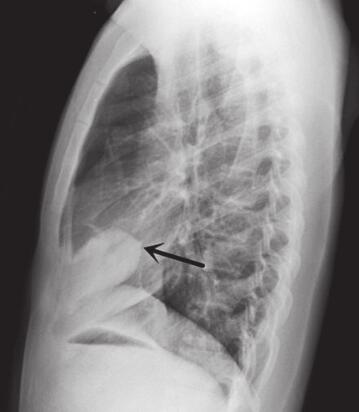

图1 2012年11月13日胸部正侧位片

右肺心膈角处见一椭圆形密度增高影,约4.5cm×6.4cm大小,边缘光滑(图A白色箭头),其前缘与胸膜关系密切,后上缘有一尖角与斜裂相连(图B黑色箭头)。右下肺膈顶下方可见一小结节影(图A黑色箭头),侧位显示不清